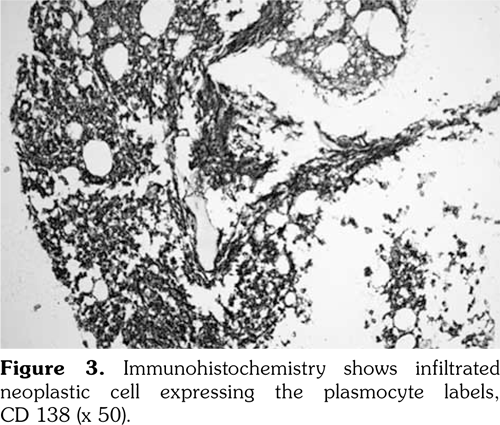

However, two years after the diagnosis of basal-cell carcinoma, the patient was re-admitted to the hospital due to complaints of feebleness, palpitation and cough lasting for 10 days. Laboratory analysis showed an increased white blood cell count of 20x109 L (NR 4-10x109/L), decreased red blood cell count of 1.28x1012/L (NR 3.5-5.0x1012/L), and platelet count of 45x109/L (NR 100-300x109/L). Serum electrophoresis revealed monoclonal protein of 68.24%. The urinary lambda (l) light chain was 0.186 (NR <0.05). Bone marrow biopsy revealed diffuse fibrosis with collagen deposition, heavy infiltration of neoplastic plasma cells (CD138, PC positive), and l light chain restriction (Figure 2-4) with a total ratio of 66% for original and naive plasma cells. Hence, the diagnosis of l plasmacytic leukemia was confirmed. However, our patient rejected to undergo further evaluation and treatment due to personal reasons.